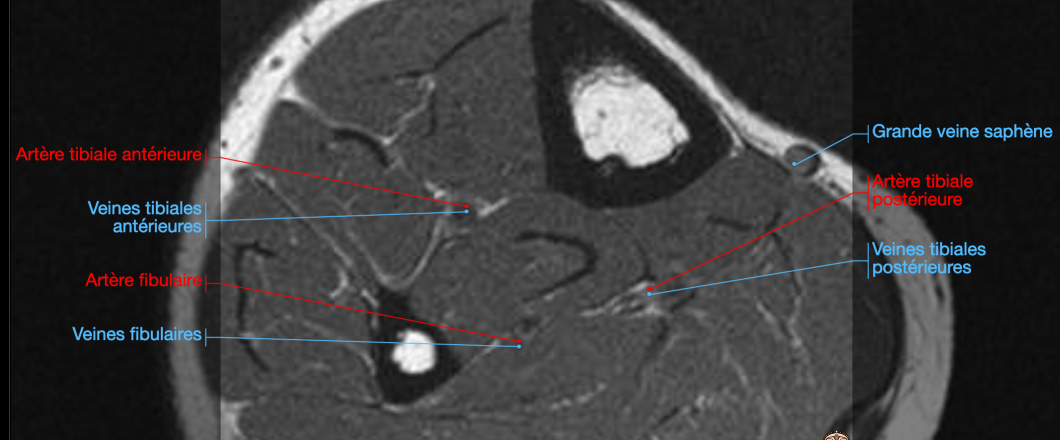

Veine tibiale antérieure

Tronc tibioperonier

Veine péronière (fibulaire)

Veine tibiale postérieure

Veines Jambières